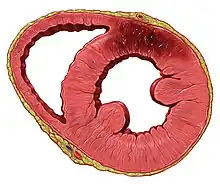

If impaired blood flow to the heart lasts long enough, it triggers a process called the ischemic cascade; the heart cells in the territory of the blocked coronary artery die (infarction), chiefly through necrosis, and do not grow back. A collagen scar forms in their place.[71] When an artery is blocked, cells lack oxygen, needed to produce ATP in mitochondria. ATP is required for the maintenance of electrolyte balance, particularly through the Na/K ATPase. This leads to an ischemic cascade of intracellular changes, necrosis and apoptosis of affected cells.[74]

Cells in the area with the worst blood supply, just below the inner surface of the heart (endocardium), are most susceptible to damage.[75] Ischemia first affects this region, the subendocardial region, and tissue begins to die within 15–30 minutes of loss of blood supply.[76] The dead tissue is surrounded by a zone of potentially reversible ischemia that progresses to become a full-thickness transmural infarct.[74][76] The initial "wave" of infarction can take place over 3–4 hours.[71][74] These changes are seen on gross pathology and cannot be predicted by the presence or absence of Q waves on an ECG.[75] The position, size and extent of an infarct depends on the affected artery, totality of the blockage, duration of the blockage, the presence of collateral blood vessels, oxygen demand, and success of interventional procedures.[29][70]

Tissue death and myocardial scarring alter the normal conduction pathways of the heart, and weaken affected areas. The size and location puts a person at risk of abnormal heart rhythms (arrhythmias) or heart block, aneurysm of the heart ventricles, inflammation of the heart wall following infarction, and rupture of the heart wall that can have catastrophic consequences.[70][77]